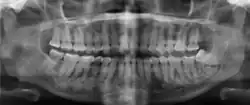

Diagnostic methodX-ray, CBCT scan, vitality testing of teeth

Diagnosis is based on clinical and radiographic observations, and in rare cases, biopsy may be performed.[3] Diagnosis is important so that the treating doctor does not confuse it for another periapical disease such as rarefying osteitis or condensing osteitis. Incorrect diagnosis could lead to unnecessary root canal treatments, or biopsy or surgical intervention which can be invasive and increase the risk of infection.[5] A pulp vitality test such as a cold test or electric pulp test can aid in diagnosis, since COD generally does not compromise pulp vitality.[6] COD can be found in individuals of all ages and ethnic backgrounds, but it has been observed more frequently in individuals of African, East Asian, and Asian descent.[7] Cone-beam computed tomography (CBCT) has proven useful in distinguishing between COD and periapical cysts, when examined with quantitative texture analysis using specialized software.[5]

xray and CBCT scans of periapical cemental dysplasia